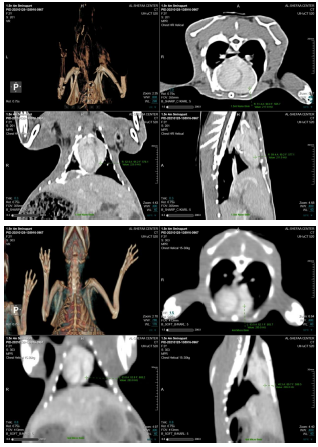

After preparing the rabbit for examination and in the case of anesthesia with the specified dose of the contrast, the rabbit was lying on the examination table to perform the spiral CT-Scan as shown in Fig. 2.

In the current study, the rabbits were used in the computed tomography (CT-scan) examination, the iodine solution, and the iodine nanoparticles contrast media to compare the effectiveness of nanoparticles within its survival in the different organs during the examination by comparing with time remaining in the organ.

The study included different organs of rabbits such as the heart, kidney, liver, bladder, and brain using iodine and iodine nanoparticles as contrast media to monitoring the [13] contrast media in 0, 5, 10, 20, 30, and 60 minutes as shown in table 1.

In this study, the rabbit was used in vivo study by CT-Scan with iodine nanoparticles of contrast medium as an alternative of iodine solution, the imaging of CT for the different rabbit organs.